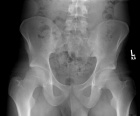

20 year old male with a six month history of low back and buttock pain

Zoom image: Radiological image Radiological image.